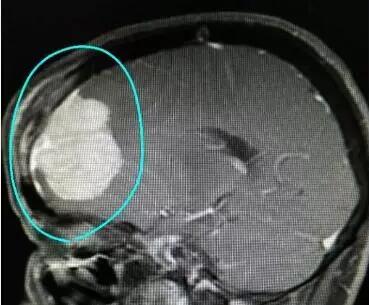

CT下顯示譚阿姨腫瘤部位

據(jù)王日升主任介紹,術(shù)中見腫瘤位于右側(cè)額葉,大小約4×4厘米,緊鄰并壓迫和侵犯矢狀竇,同時也累及顱骨和頭皮。經(jīng)過在顯微鏡下仔細操作,終于完整切除了腫瘤。并且同時用鈦網(wǎng)修補了缺損的顱骨,使病人術(shù)后頭部外觀和原來一樣。手術(shù)持續(xù)4個小時,非常成功。